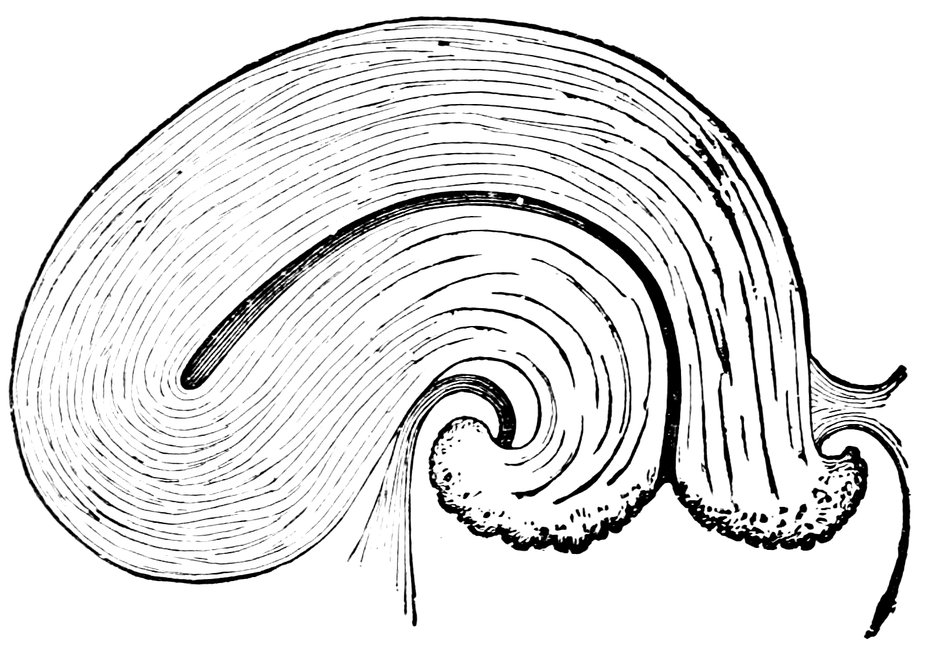

| 16. | Ripening follicles | 61 |

| 17. | Graafian follicles | 62 |

| 86. | Diagrammatic Representation of the Graafian Follicle | 585 |

| 89. | 586 | |

| 90. | 587 | |

| 91. | 588 | |